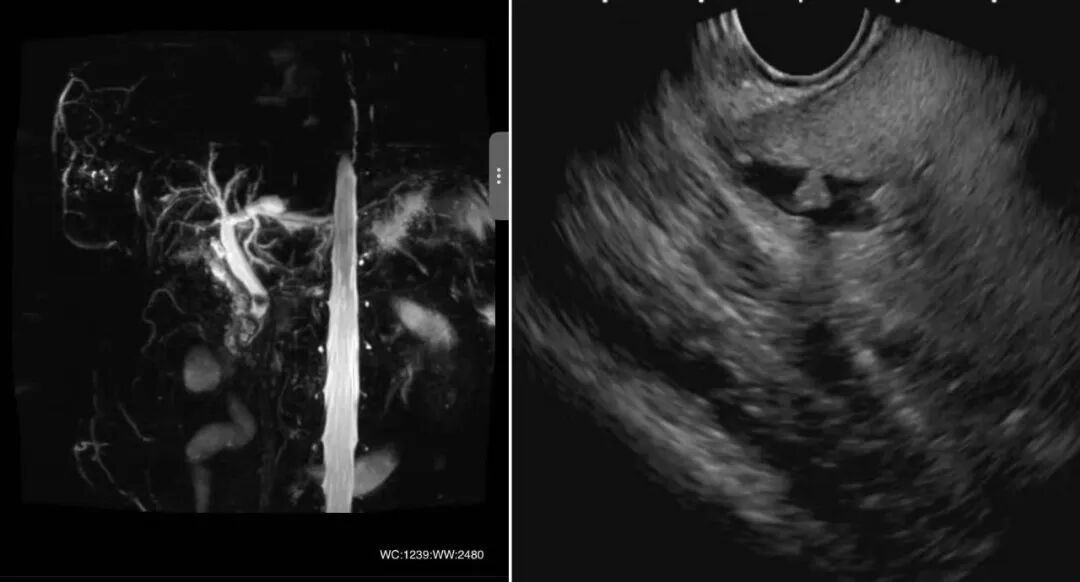

脾胃病科主任乔会侠带领团队为患者进行全面检查,术前运用超声内镜对结石位置和大小进行精确探查,为手术奠定坚实基础。

术中造影发现,胆管全段可见多发直径约1.0-1.5cm不规则充盈缺损;运用子镜直视观察发现,胆管全段可见多发黄褐色巨大结石,且部分结石质地坚硬。常规取石网篮套取存在网篮嵌顿风险,宋扬选用取碎一体网篮套取结石依次取出,较大结石行碎石取出,成功疏通“生命通道”。

肝胆胰系统曾被称为“消化道的最后盲区”,传统的ERCP只能进入十二指肠降部,通过造影进行观察,呈现的是二维图像,无法对胆胰管内部进行直视化观察,也无法对胆胰管内部病变进行精准地诊断及治疗。ERCP联合胆胰子镜直视系统,突破了传统内镜诊疗盲区,可清晰探查胆胰管疾病,并进行精准诊断和治疗,实现了胆胰疾病诊疗直视化、高清化。